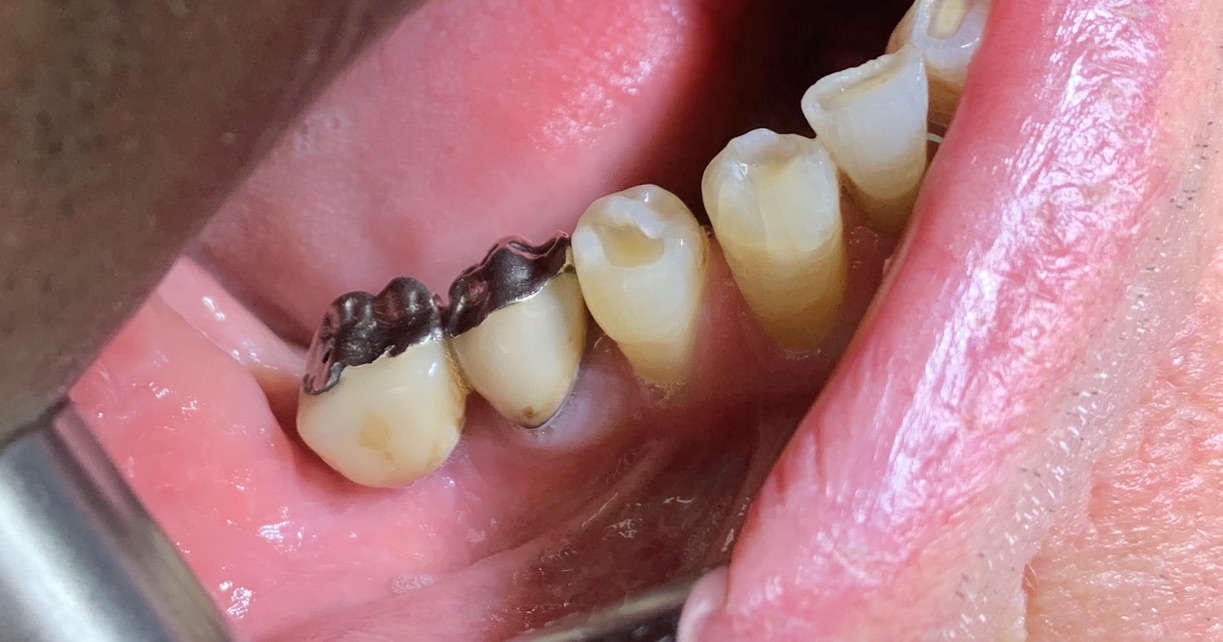

4 - TRAMONTE IMPLANT IN ADVANCED AGE

A patient with Tramonte implants for 28 years needs more implants, but is now almost 90 years old and takes a lot of medicines.